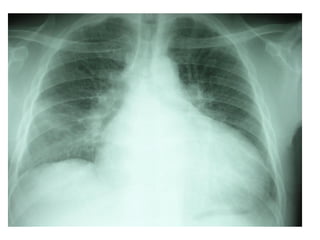

XQUANG TIM PHỔI

Xquang thẳng

 Cung dƣới phải giãn (NP)

 Mỏm tim nâng cao

 Cung ĐMP giãn

 Phổi mờ nhiều (ứ huyết)

TRIỆU CHỨNG CẬN LÂM SÀNG

Xquang nghiêng trái

 Khoảng sáng sau xƣơng ức

hẹp lại (do thất phải to)